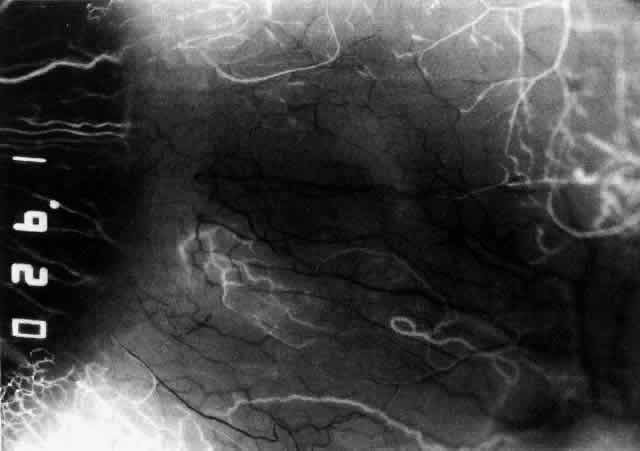

The characteristic features of necrotizing scleritis on fluorescein angiography are hypoperfusion and, eventually, nonperfusion of the vascular networks (Figs. 40 through 43).26 The initial changes are on the venous side of the capillary network; the transit time of the dye increases even if the eye is red and congested. If the disease process persists or has been present for a long time, thrombosis and permanent vaso-occlusive changes occur. These vessels (or the occluded capillary network) are bypassed by the opening of anastomotic channels. New vessels in a granuloma give rise to deep intrascleral leakage of dye (see Fig. 43). Conjunctival and episcleral involvement by the destructive change is late but is always preceded by vaso-occlusive changes that can sometimes be detected with use of the red-free light on the slit lamp (Figs. 44 and 45).

Uveitis, lens changes, glaucoma and other serious complications such as central vein occlusion do not seem to occur until the disease process affects the whole circumference of the eye.27 Sometimes scleral thinning, as well as increased transparency, occurs, but unless the intraocular pressure rises above 40 mm Hg, staphylomas are extremely rare. As the disease is brought under control, the necrotic areas are absorbed or sequestered, leaving an ectasia with the underlying uvea exposed or covered with a thin film of conjunctiva or episclera (Fig. 46). If the defect is small, new collagen will cover it (Figs. 47 and 48). If the defect is large or if it is thought to have been the source of a persisting antigenic stimulus, the necrotic tissue may need to be excised and then covered by scleral grafts. However, this procedure is usually performed for aesthetic reasons rather than because the vision is endangered. The underlying disease process is not affected by the presence of a scleral graft, which has to be covered by conjunctiva and, preferably, episclera if it is to survive. Surgery must never be undertaken until the disease process has been suppressed. Temporary gluing may be used in perforated eyes until this has been achieved.